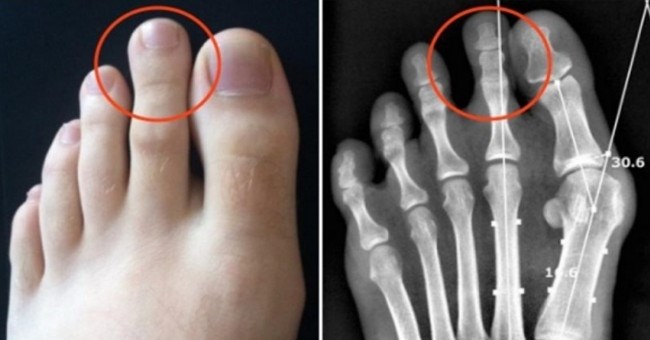

• Ngón chân trỏ dài hơn ngón chân cái và cái kết chỉ 15% dân số thế giới phải chịu

Ngón chân trỏ dài hơn ngón chân cái và cái kết chỉ 15% dân số thế giới phải chịu